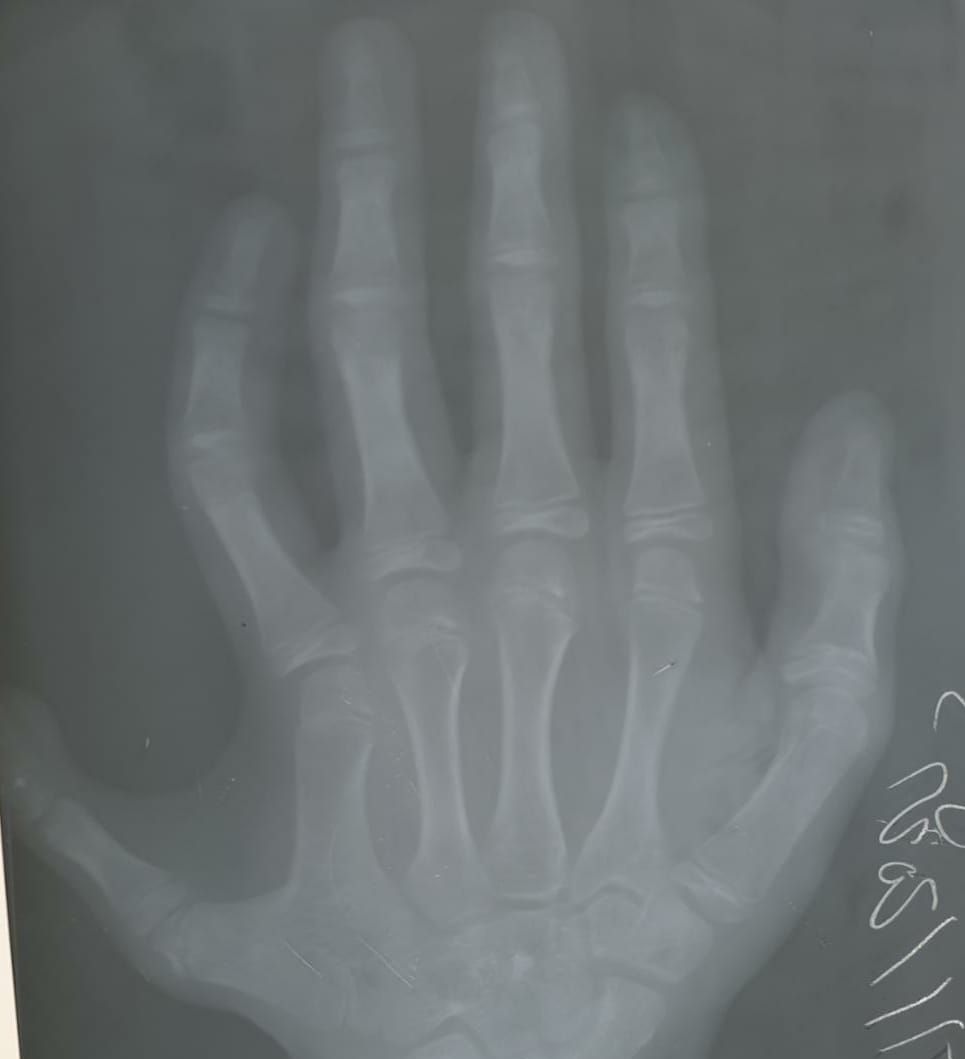

Pyetje: Jam furnizuar me (lindjen e) një vajze që ka një gisht të gjashtë në dorën e saj të majtë. Cili është gjykimi i Islamit për heqjen e tij?

Përgjigje: Nuk ka ndalesë për heqjen (operimin) e gishtit të tepërt të vajzës nëse nuk ka dëme në këtë gjë. Suksesi vjen prej Allahut dhe lëvdatat e shumta dhe shpëtimi i madh i Allahut qofshin mbi Pejgamberin tonë Muhamedin, mbi familjarët dhe shokët e tij.